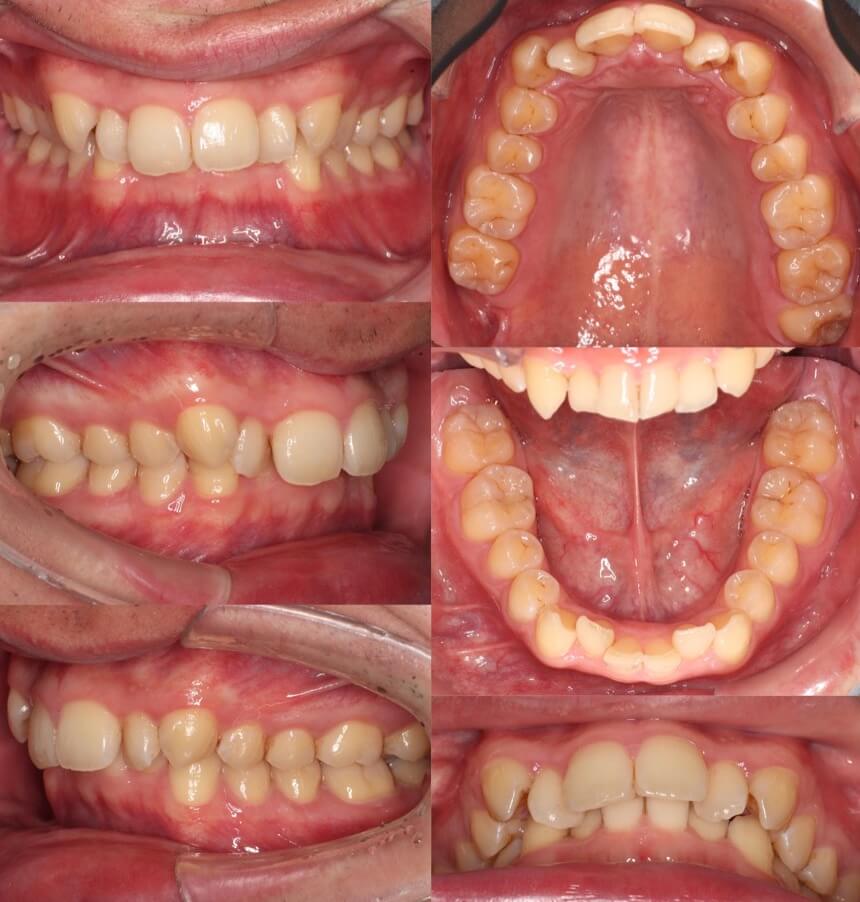

20代女性・唇側矯正装置・2本抜歯

過蓋咬合の治療方法で、上下どちらの前歯を圧下させるか、歯並びや歯の見え方で選択します。この症例は、上の前歯が下に落ちていると言うより、下の前歯が上に突き上げているタイプであったため、下の前歯を圧下させました。

<症例概要>

主訴:前歯の突出

年齢・性別:高校生女性

住まい:千葉県八千代市

症状:過蓋咬合・上顎前突

治療方針:下顎前歯の圧下・抜歯空隙の閉鎖

抜歯:上左右4番(計2本)

治療期間:2年6か月

リテーナー:上下フィックスタイプ+上下プレートタイプ

治療費用:968,000(税込)

代表的副作用:痛み・治療後の後戻り・歯根吸収・歯髄壊死・歯肉退縮

▶︎その他の副作用